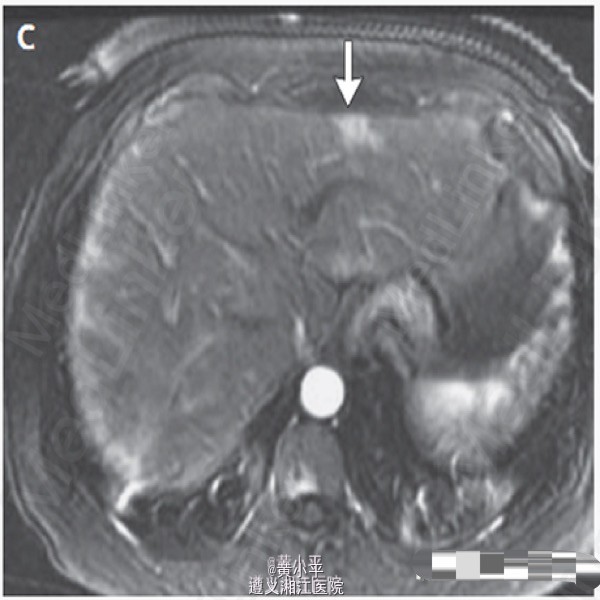

查体:BP190/97mmHg,其余生命体征正常。腹软,于右上腹可触及柔软肝脏边缘,未及肝脾肿大或腹胀。余查体正常。肝脏MRI增强发现右叶9.4cm×12.3cm×8.5cm异质性增强肿块。另有一处在第七段发现5mm病变,考虑可能为转移灶;余肝右叶多发小病灶考虑为血管瘤。(图1-3) 血浆皮质醇水平为23.5μg/dL(648 nmol/L)(参考值5-15μg/dL);血管活性肠多肽32pg /mL(参考值小于75)。入院第二天行SPECT,提示肝右叶大范围喷曲肽再摄取降低,符合MRI所示。